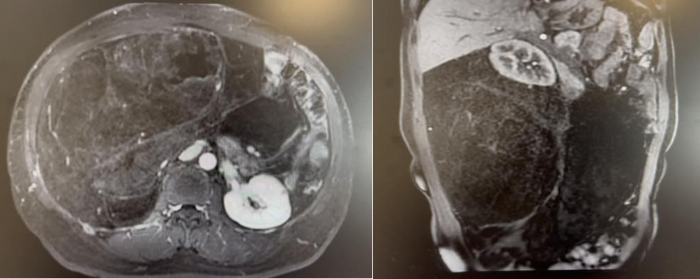

56岁男性患者,因间断上腹不适4个月,检查发现腹膜后肿瘤2周。腹部CT及核磁提示腹膜后巨大脂肪肉瘤,直径约35cm。

我们为患者实施全麻下开放腹膜后肿瘤切除术。术中可见肿瘤挤压十二指肠、胰头、肠系膜血管、下腔静脉和腹主动脉,但未侵犯结肠、肠系膜血管等组织器官,且包膜完整。手术团队仔细游离,完整切除腹膜后肿瘤,剔除腹膜后脂肪。历时2个小时完成,术中出血约100ml。

术后恢复顺利:第3天排气并进食流食;第5天恢复正常饮食;术后第9天出院。术后病理高分化脂肪肉瘤,肿瘤最大径38cm,与肾周脂肪粘连。术后3月随访,未见肿瘤复发。